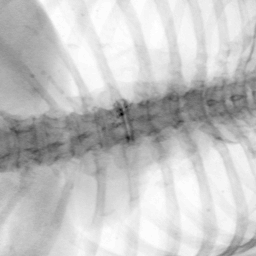

Exp. 2: Fetal brain data is used to test the robustness of our approach under real conditions. Fetuses younger than 30 weeks very often move a lot during examination. Fast MRI sequences allow artifact free acquisition of individual slices but motion between slices corrupts consistent 3D information. Fig. 3 shows that our method is able to accurately predict also under these conditions. For this experiment we use from three orthogonally overlapping stacks of ssFSE slices covering the fetal brain with approximately 20-30 slices each. We are ignoring the stack transformations relative to the scanner and treat each individually. For , 28 clinically approved motion compensated brain reconstructions are resampled into a volume with spacing. A density of 500 unique sampling normals has been chosen via the Fibonacci sphere sampling method with 25 sampling planes evenly spaced between -25 to +25 on the Z-axis. This gives a plane spacing of 2mm, sampling only the middle portion of the fetal brain. Training took approximately 10hrs for 30 epochs. Prediction, i.e., the forward pass through the network, takes approx. 12 ms/slice.

Exp. 3: Adult thorax data: To show the versatility of our approach we also apply it to adult thorax scans. For this experiment no organ specific training is performed but the whole volume is used. We evaluate reconstruction performance similar to Exp. 1 and prediction performance when is projected on an external plane, comparable to X-Ray examination using C-Arms. The latter provides insights about our method’s performance when applied to interventional settings in contrast to motion compensation problems. 60 healthy adult thorax scans were randomly selected, 51 scans used for and nine scans used for . Each scan is intensity normalised and resampled in a volume of with spacing . Using the Fibonacci sampling method, 25 sampling plane of size , evenly spaced between -50 and +50, were rotated over 500 normals. Training took approximately 20 hours for 60 epochs. Fig. 4c shows an example reconstruction result gaining 28dB PSNR with additional SVR. prediction takes approx. 20 ms/slice for this data.

Discussion & Conclusion: We have presented a method that is able to predict slice transformations relative to a canonical atlas co-ordinate system. This allows motion compensation for highly motion corrupted scans, e.g., MRI scans of very young fetuses. It allows to incorporate all images that have been acquired during examination and temporal proximity is not required for good initialisation of intensity-based registration methods as it is the case in state-of-the-art methods. We have shown that our method performs remarkably well for fetal brain data in presence of surrounding tissue and without organ specific training for low-dose thorax CT data and X-Ray to CT registration.